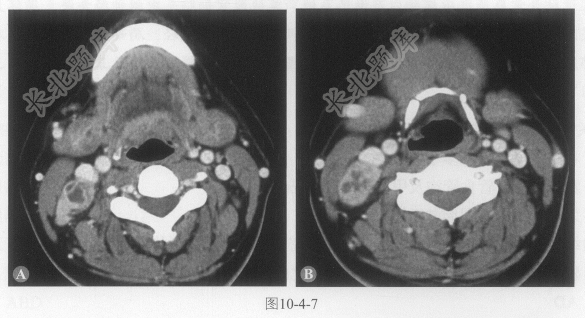

患者女性,39岁,发现右颈肿物10余天。颈部CT如图10-4-7。

- 多项选择题1.关于颈部CT扫描,正确的描述是:

A、右侧颈部Ⅱ区淋巴结肿大,边界清楚

B、右侧颈部Ⅱ区淋巴结肿大,边界模糊

C、不均匀强化,内见多发低密度区及分隔,呈“花环状”改变

D、明显强化,内可见囊变及囊壁强化的壁结节

E、淋巴结明显融合,侵犯周围结构